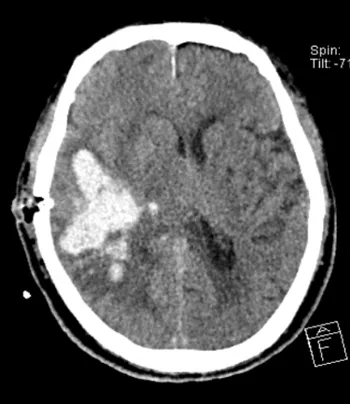

術(shù)后

復查頭顱CT顯示

顱內(nèi)血腫顯著減少